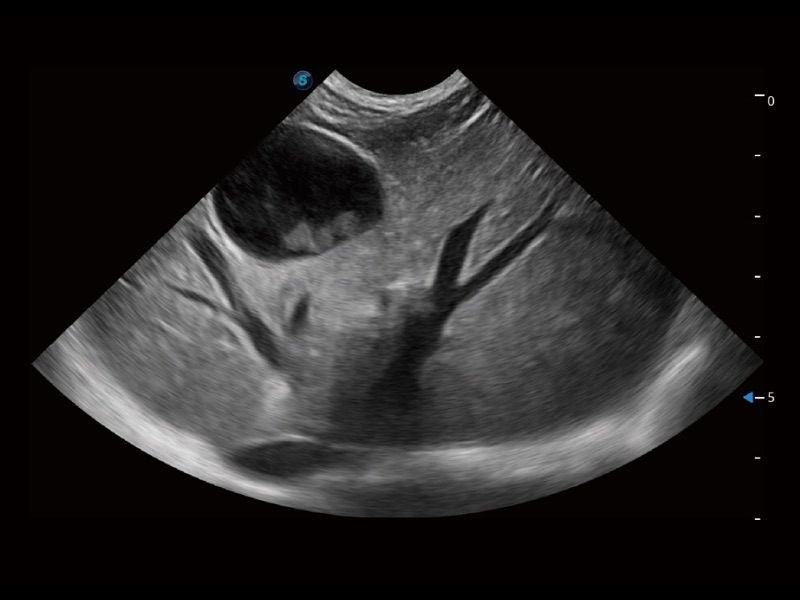

(猫)胆囊

(犬)肝脏